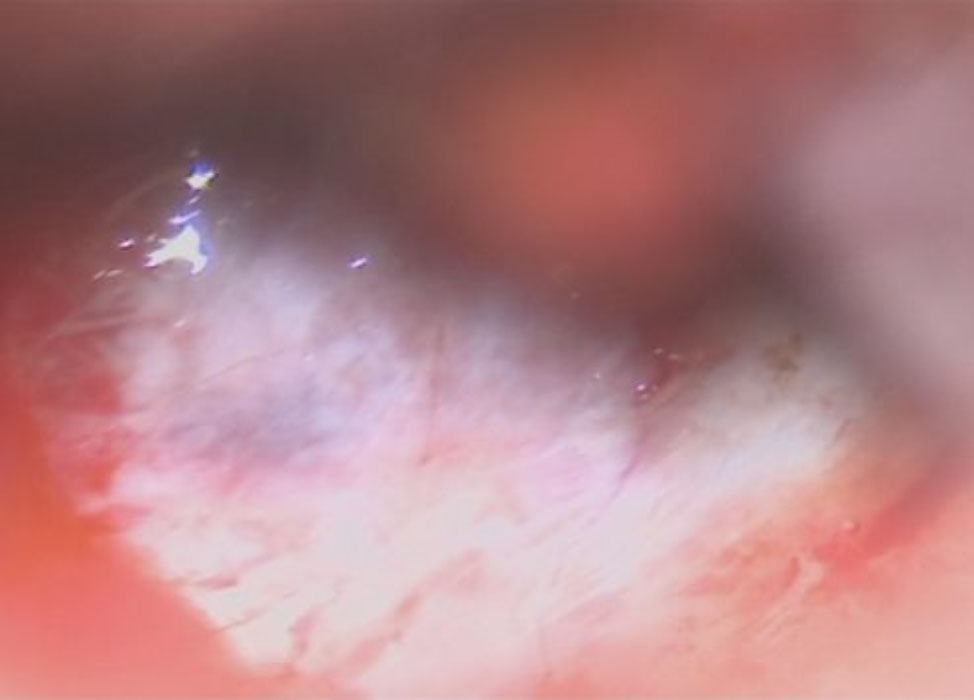

摘出 中

摘出 後